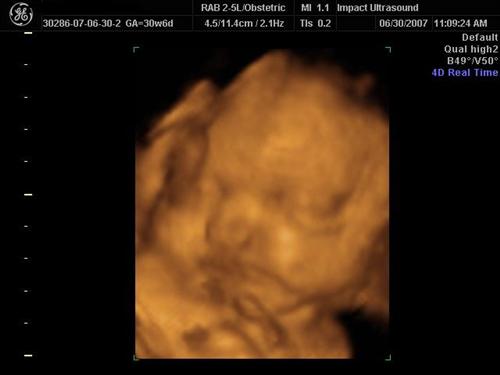

We went to Impact Medical Technologies today for our 3D/4D sono! It was alot of fun! Our normally sleepy, non-cooperative baby was awake and soooo active the entire time! They got some really great shots of her! Here are a few!

She's licking her hand here: